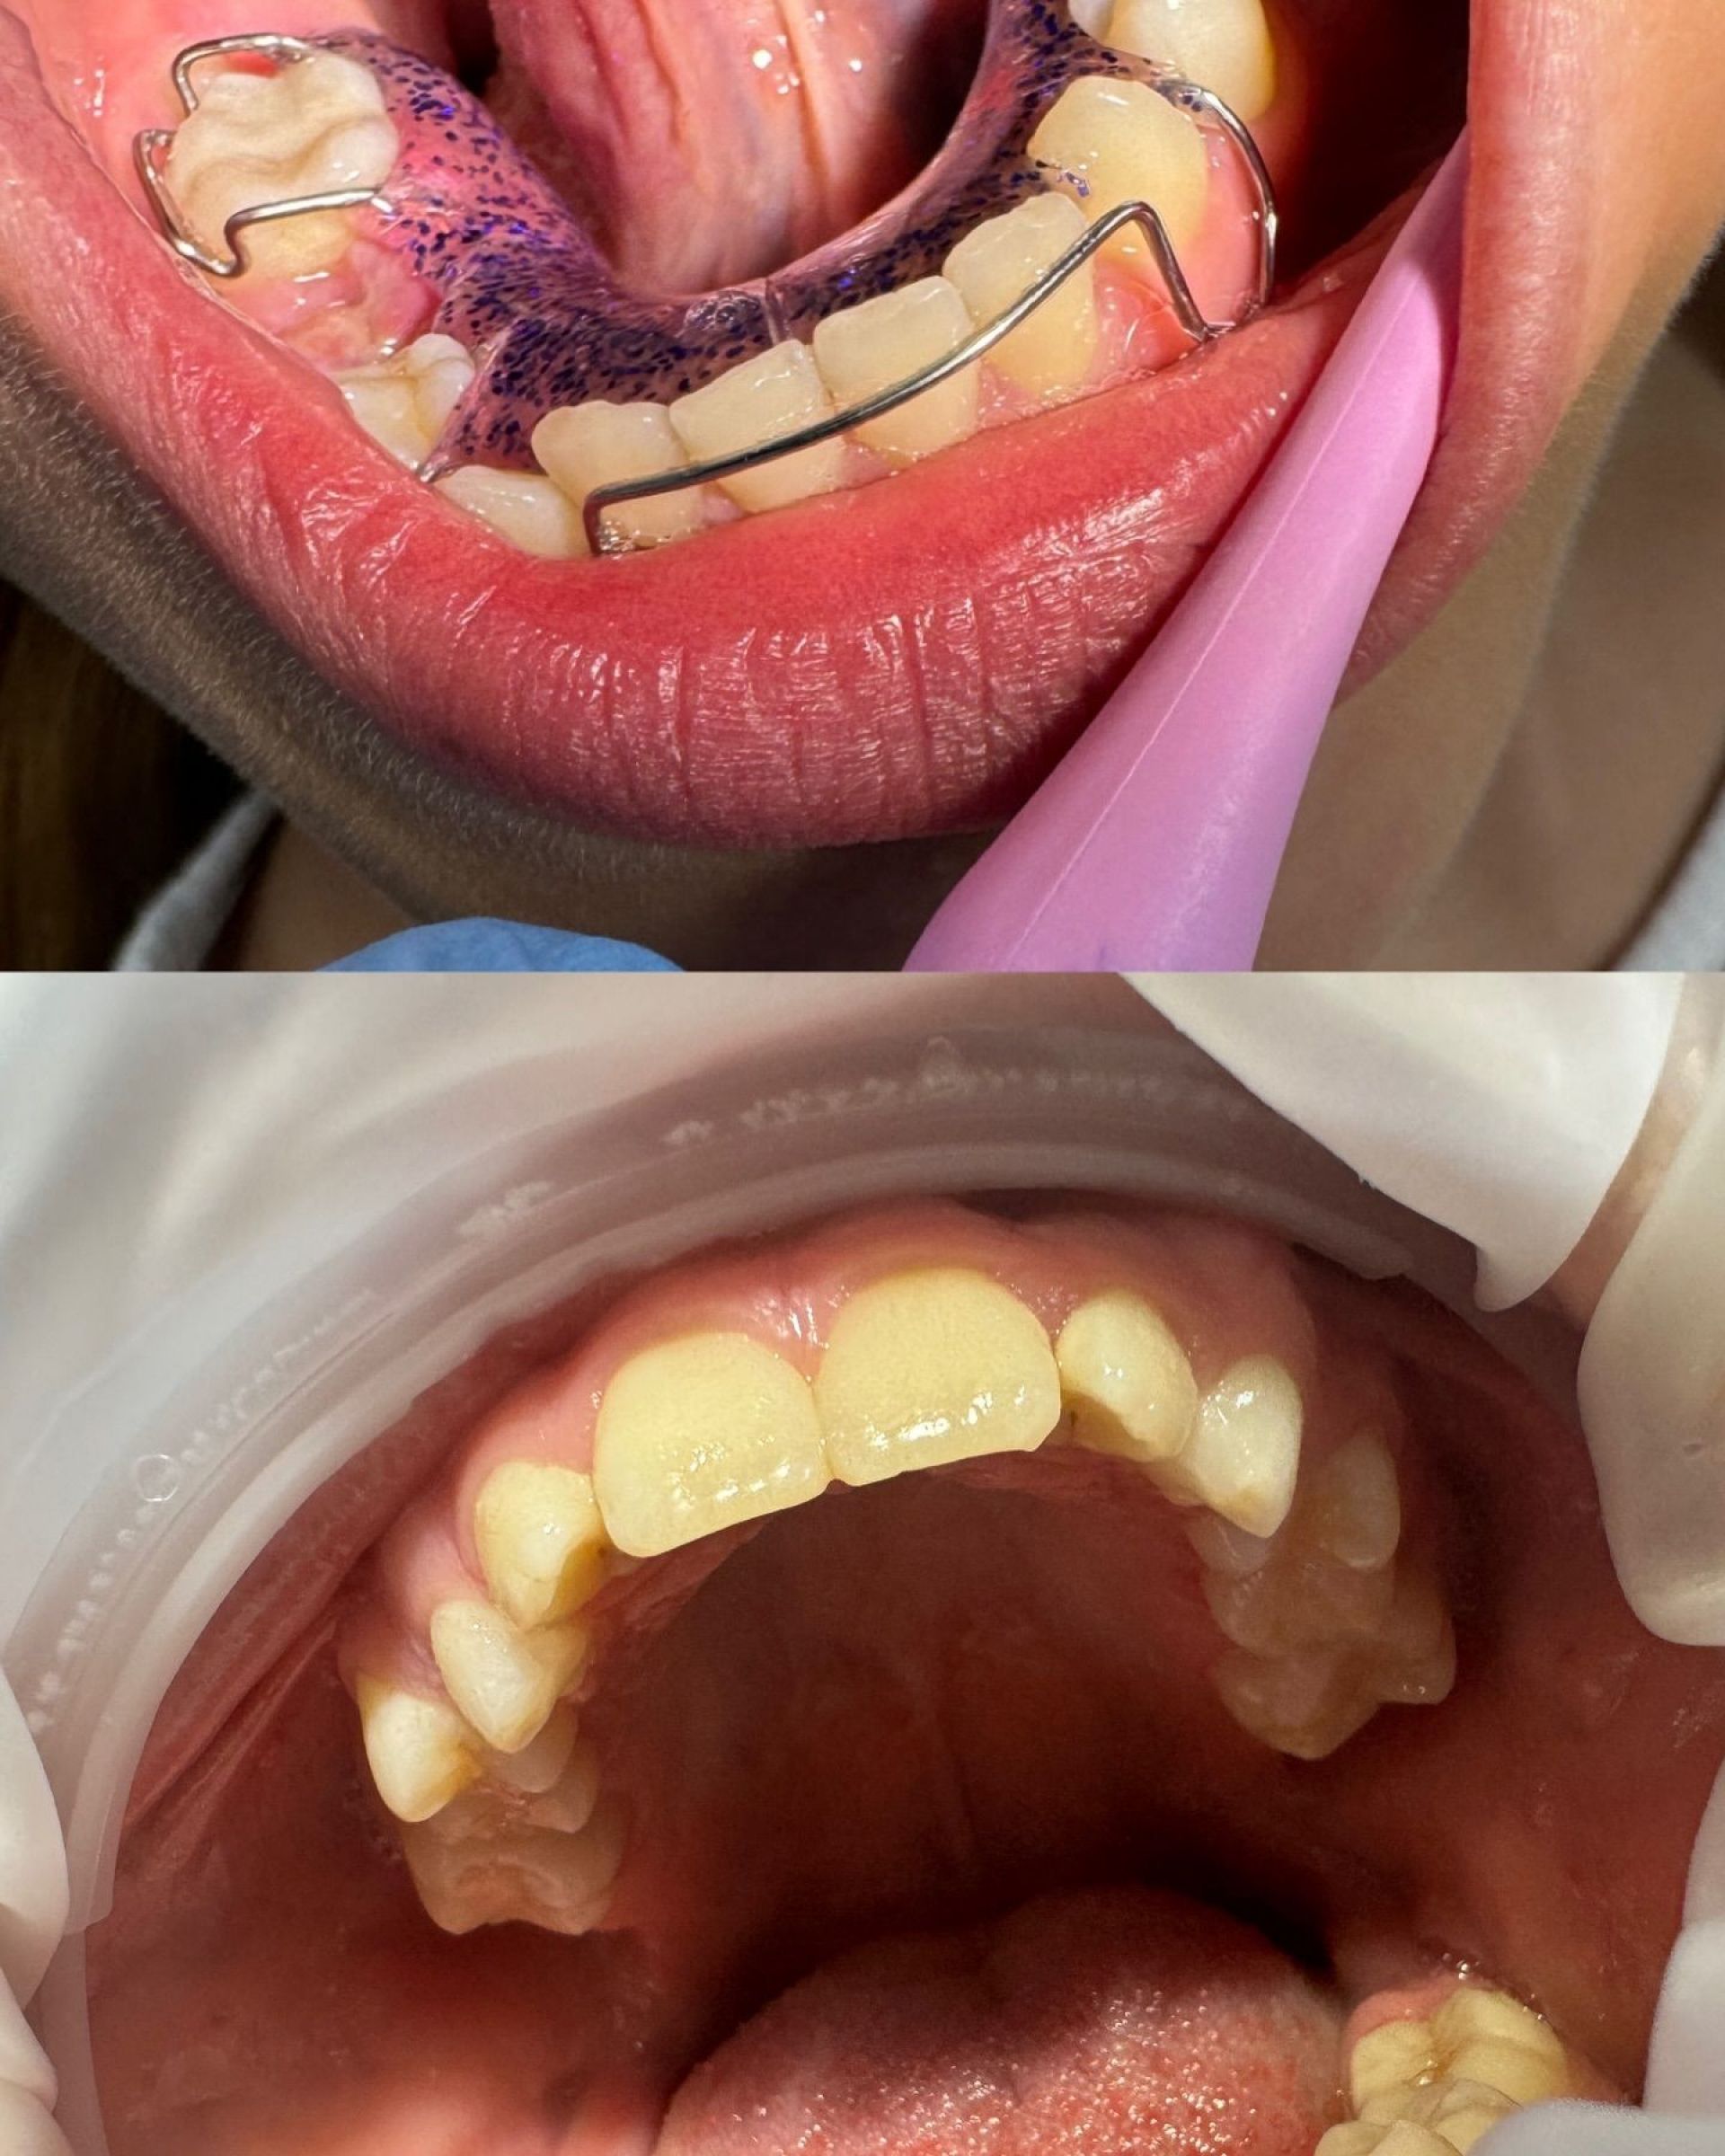

Стоматолог-ортодонт Белінський Владислав

Стоматолог-ортодонт Владислав Андрійович Белінський – це спеціаліст, який надає кваліфіковану стоматологічну допомогу дітям, орієнтуючись на сучасні стандарти якості та безболісне лікування. Він приділяє особливу увагу кожному маленькому пацієнту, створюючи комфортну атмосферу і забезпечуючи ефективне лікування без стресу для дитини.

Лікар-ортодонт допомагає у вирішенні проблем із прикусом та неправильним розміщенням зубів, що є дуже важливим у дитячому віці для формування здорової зубної архітектури в майбутньому. Владислав Андрійович використовує інноваційні методи та сучасні технології для досягнення найкращих результатів.

Для дітей він пропонує встановлення брекетів, елайнерів, пластинок і вінірів, що сприяють правильному формуванню прикусу та зубного ряду. Завдяки індивідуальному підходу кожна дитина отримає найкраще лікування відповідно до її потреб.

- Встановлення брекетів, елайнерів, пластинок.